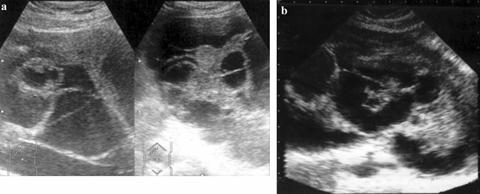

Chist ovarian seros multilocular. a. Sectiune transversala, cu evidentierea a trei structuri esentiale in diagnosticul chistului ovarian: vezica urinara plina, corpul uterin, formatiune ovariana ce prezinta contururi bine delimitate, ecourile interne fiind organizate si desenand septurile intratumorale. b. Sectiune longitudinala. c. Chist ovarian mucoid. Peretele posterior al formatiunii tumorale mulat pe coloana vertebrala.